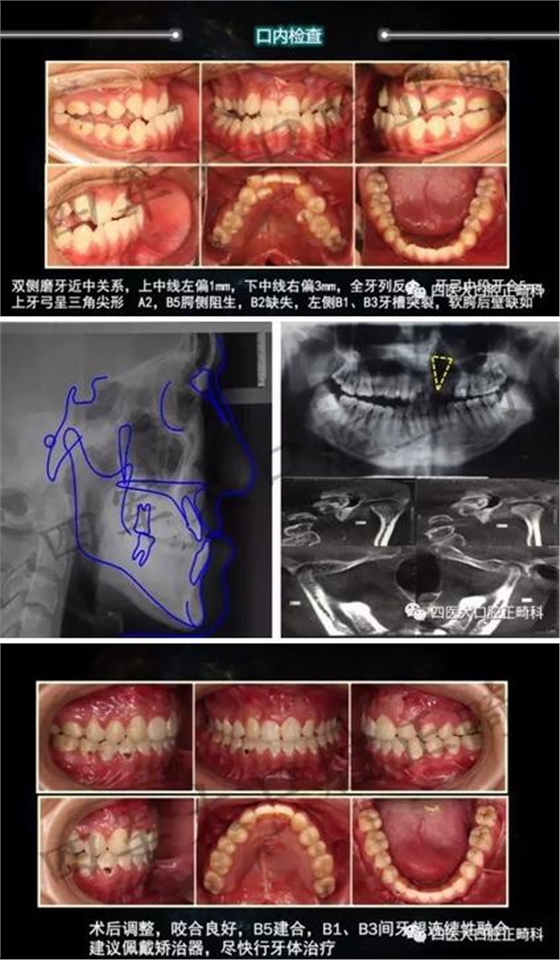

有這樣的情況嗎?